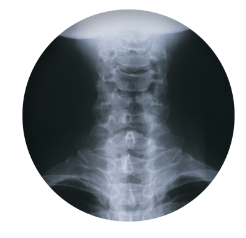

다음과 같은 자궁 경부 디스크 관련 정보에 대해 자세히 알아보십시오. B. 경추 디스크 증상, 원인 및 치료 방법. 경추추간판은 사람의 척추의 경추 또는 흉추에 위치한 추간판(보철물)이 변형되어 발생하는 질환으로 흉통, 요통 등이 발생한다. 보통은 원인불명의 자연회복을 기다리는 것이 가장 좋으며, 통증이 심한 경우에는 항염증제나 근육이완제 등을 식이보충제로 사용하기도 합니다. 압력이 심하면 수술이 필요할 수 있습니다. 예방 조치에는 좋은 자세, 체중 조절, 충분한 운동, 목과 등 근육 강화가 포함됩니다.

목디스크는 경추나 흉추에 있는 디스크(보철물)의 변형으로 인해 발생하는 질환으로 다음과 같은 증상이 나타날 수 있습니다.

목의 추간판 탈출증은 다음과 같은 원인으로 인해 변형된 디스크(의치)로 인해 발생하는 상태입니다.